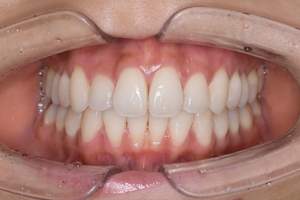

PMTC・オフィスホワイトニング

治療前

治療後

| 年齢 | 46歳・男性 |

|---|---|

| 主訴 | 着色を取りたい・歯を白くしたい |

| 治療内容 | PMTC・オフィスホワイトニング |

| 治療期間 | 90分 |

| 費用 | PMTC 5,500円 オフィスホワイトニング2回 6,600円(自費 診療) |

| リスク・副作用 | ・生活習慣(喫煙・コーヒーなど)により再度着色することがあります ・詰め物や被せ物はホワイトニングでは白くなりません ・ホワイトニングの効果は永久的なものではなく徐々に色戻りが起こります ・ホワイトニング後は歯の表面の水分量が一時的に少なくなりしみることがあります ・保険適用外の施術です |